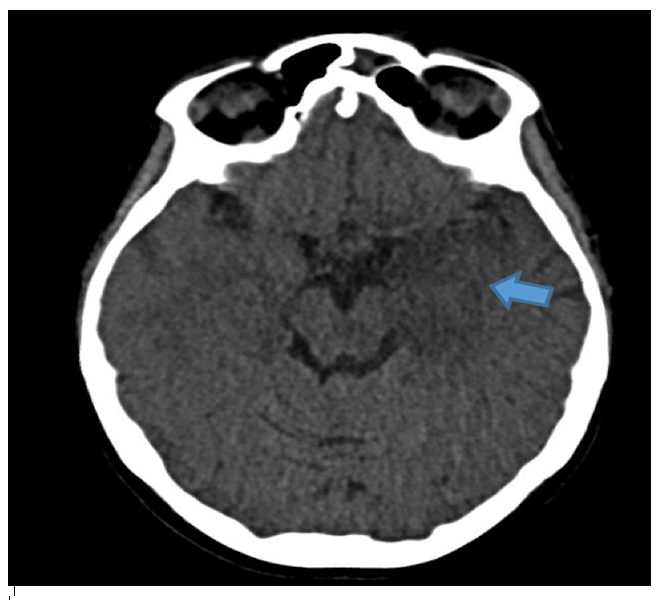

A 35-week pregnant woman was diagnosed with dengue fever. Within three days, she developed confusion and seizures, requiring emergency caesarean section and mechanical ventilation. Brain computed tomography revealed a hypodense lesion in the left temporal lobe with mass effect compatible with limbic encephalitis (Figure 1). Cerebrospinal fluid (CSF) analysis showed 40 cells/mm³ and 80 mg/dL of protein. Empirical intravenous acyclovir (10 mg/kg every 8 h) was initiated because of the presumptive diagnosis of herpetic encephalitis. After 9 d, she was extubated but remained cognitively impaired and was discharged 11 d later with partial neurological recovery. Two days later, she was admitted to a tertiary referral hospital with fever and generalized weakness. Brain magnetic resonance imaging (MRI) demonstrated the involvement of limbic structures, hyperintensities in the cortical and subcortical brain parenchyma with subtle mass effects, cortical enhancement in these regions, and findings consistent with volume loss in the left mesial temporal lobe and insular cortex, likely resulting from previous encephalitis (Figure 2). MRI revealed demyelinating lesions in the cervical and thoracic spinal cord (Figure 3). CSF analysis showed 57 cells/mm³, more than 300 mg/dL protein, and glucose of 42 mg/dL. Molecular tests, including those for dengue and herpesviruses, as well as metagenomic sequencing of CSF, were negative. A comprehensive panel for autoimmune encephalitis in both the blood and CSF also yielded negative results. She received pulse methylprednisolone for 5 d, followed by intravenous immunoglobulin for 5 d, with slight cognitive improvement.

FIGURE 1: Initial CT scan of the patient. Hypodense lesion in mesial left temporal lobe with mass effect (blue arrow). Limbic encephalitis was suspected